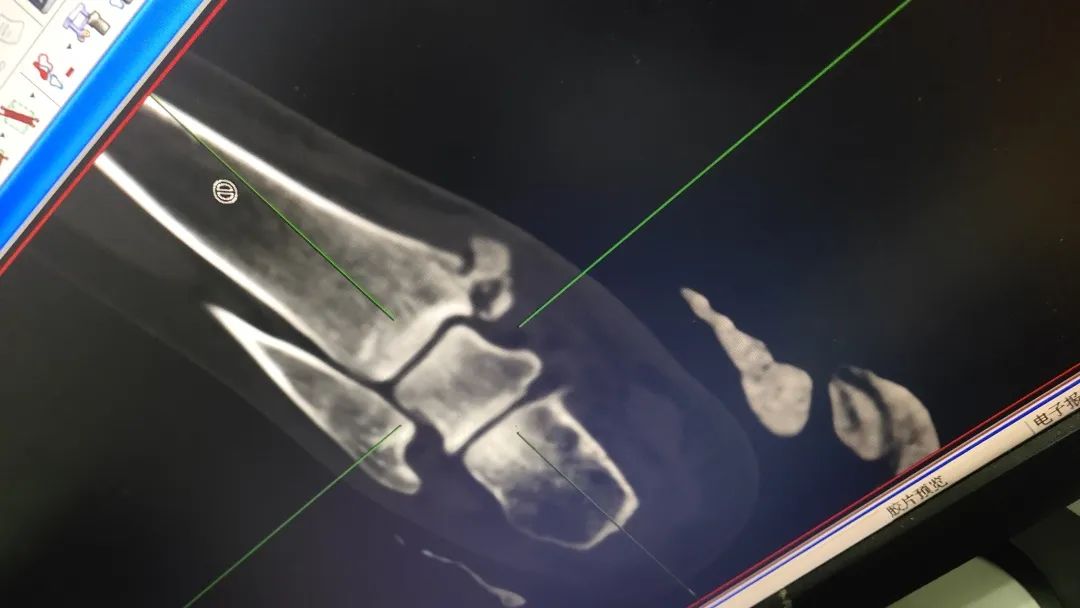

住院记得带好病历,影像片子(无论是胶片还是电子图像,如果是DICOM格式可能得带上笔记本),各种检查、检验报告。衣服不用带太多,甚至可以只带一套留着出院的时候穿就可以了,毕竟住院的时候每天都有阿姨来发干净的病号服。